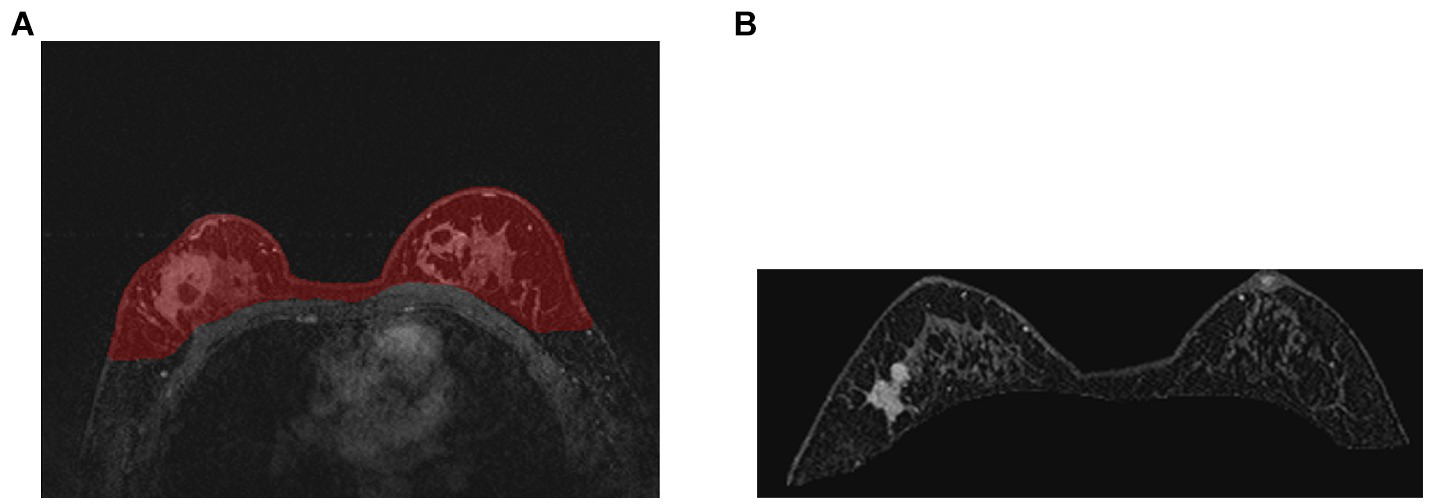

The training curve is shown in Figure 6 and examples of segmented mammary glands are shown in Figure 8.

Figure 8

Examples of segmented mammary gland. (A) shows the mammary gland region in red, (B) shows a segmented mammary gland.

The performance of the proposed method for mammary gland segmentation is shown in Table 5. We achieved 93% IoU in the first segmentation task.